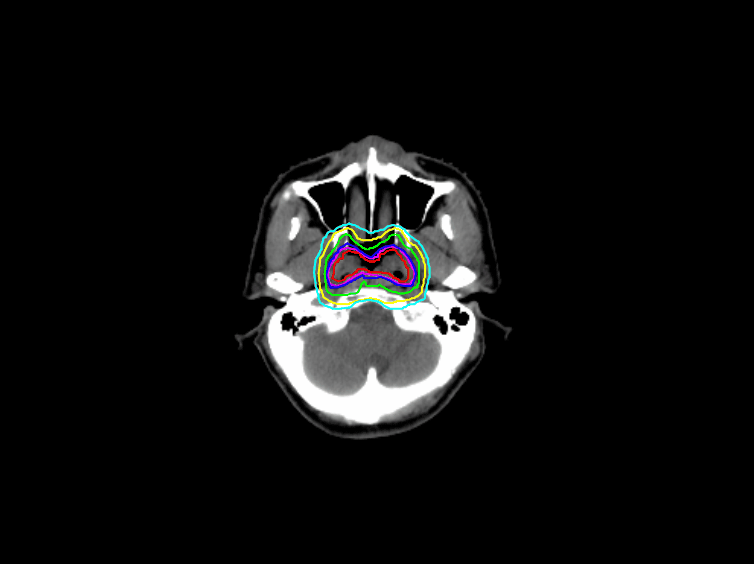

柏视医疗自主研发的放疗靶区智能勾画解决方案,包括全身危及器官自动勾画以及肿瘤靶区(GTV)、临床靶区(CTV)的智能勾画;采用了深度学习和传统影像分割法相结合的技术、加入临床知识和多种图像处理方法,仅需数十例数据对算法模型进行训练,就可以获得高精度的勾画结果。

经过测试,全身OAR勾画的平均Dice值高于0.9;GTV的勾画风格也可根据科室内部的勾画习惯进行个性化定制;该方案采用B/S架构,通过任意一台电脑的谷歌浏览器访问到指定服务器就可以进行自动勾画。